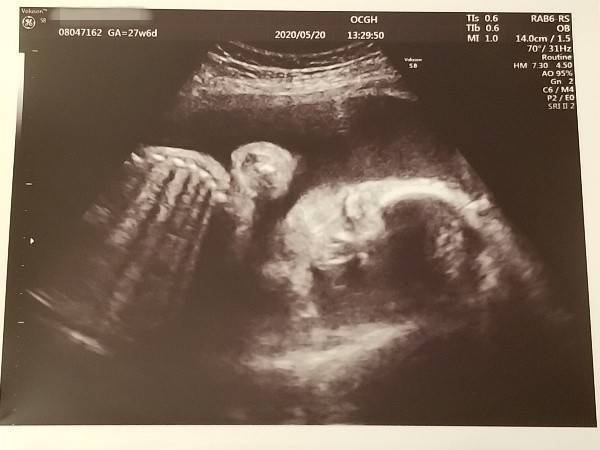

▽エコーはちょっとぼやけちゃったのだけど(^^;